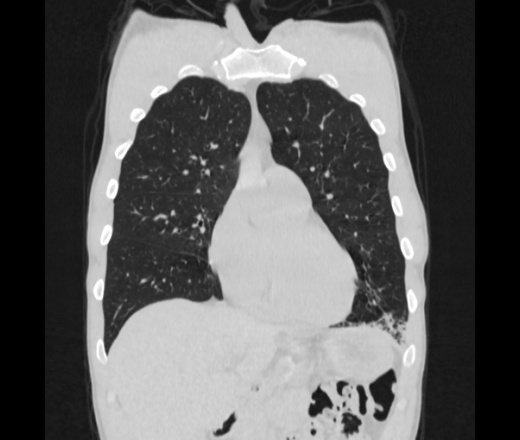

Мужчина пенсионного возраста. Цель назначения КТ ислючение зла в левом легком. Вижу тракционные бронхоэктазы с рубцовой эмфиземой по периферии, скорее всего БЭБ в стадии обострения. Дивертикулы трахеи. Выложил из за того что есть доля сомнения в отношении исключения зно3, немного смущают линии похожие на Керли.